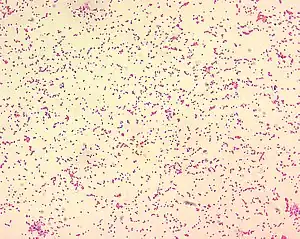

| Brucella spp. are gram-negative in their staining morphology. Brucella spp. are poorly staining, small gram-negative coccobacilli (0.5-0.7 x 0.6-1.5 µm), and are seen mostly as single cells and appearing like "fine sand". | |